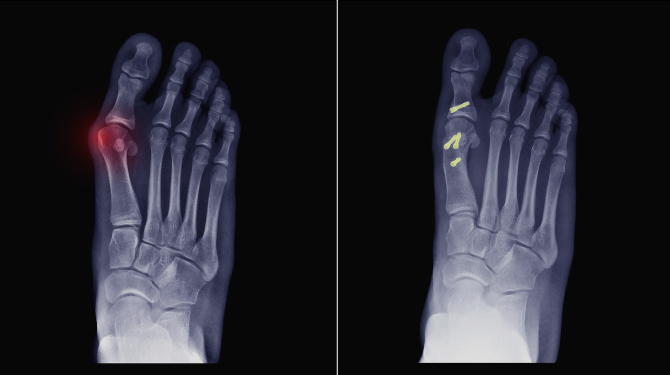

a. Osteotomy (Bone Realignment Surgery)

The surgeon cuts and repositions the bone to correct alignment.

c. Internal Fixation (Plates, Screws, Nails)

Used for precise correction and stabilization of the bone.